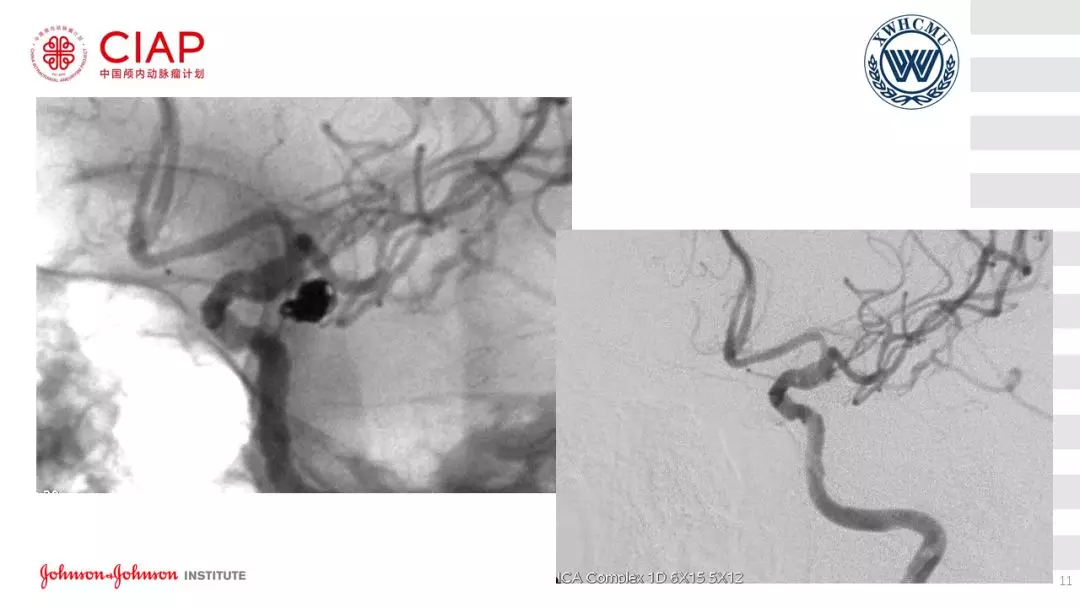

张鹏教授:不同辅助方法下栓塞动脉瘤弹簧圈的选择